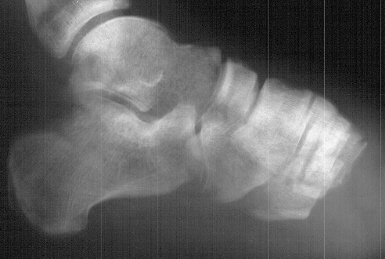

RADIOGRAPHS:

AP and lateral views of the right lower extremity revealed a Salter Harris III proximal tibial fracture with intraarticular extension into the medial and lateral tibial plateaus. The epiphysis was anteriorly displaced on the metaphysis.